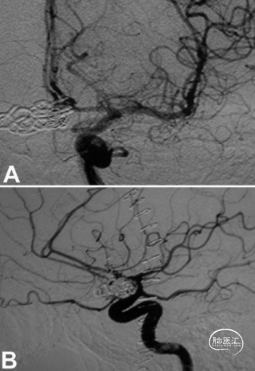

该例39岁男性患者从另一家医院转来,主诉为急性剧烈头痛,持续1天,对镇痛药无反应,神经系统检查结果正常。计算机断层扫描没有发现任何出血迹象,显示一个鞍上肿块,提示有动脉瘤。磁共振成像随后证实这一发现。腰椎穿刺没有发现蛛网膜下腔出血的迹象。脑血管造影显示,左侧A1-A2交界处有一个宽基、大型ACoA动脉瘤和两个小型动脉瘤。两个A2节段供血均来自左侧A1节段,推测右侧A1段缺如或发育不良(图1)。

患者没有出现任何神经功能障碍,术后恢复顺利。术后血管造影证实动脉瘤已完全闭塞(图4)。